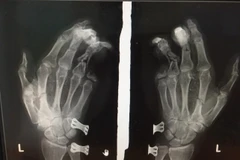

Trong lúc đang sử dụng điện thoại, một thiếu niên 14 tuổi ở Hải Dương đã bị nát bàn tay trái, vết thương dập nát da gan tay và cơ ô mô cái, sai hở lộ khối xương trụ cốt, gãy hở các xương bàn.

Ngày 28/4, Bệnh viện Đa khoa tỉnh Sơn La đã tiếp nhận bệnh nhân nam Lò Văn Yến (sinh năm 2009, trú tại bản Pá Ngà, xã Mường Giôn, huyện Quỳnh Nhai, tỉnh Sơn La) trong tình trạng chấn thương nguy kịch